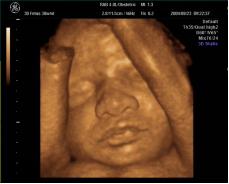

随着宝宝在妈妈肚子里一天天长大,准妈妈渴望知道宝宝在妈妈肚子里的情况,宝宝在里面什么样子?现在,三维彩超可以让你如愿以偿。

海宁康华医院引进飞利浦、GE高端彩超设备,开展胎儿三维超声检查,能够立体显示出宝宝在子宫中的实时图像,观察胎儿的生长发育情况,让每一位准妈妈尽早感受到为人母的幸福和喜悦。